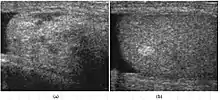

Fig. 6. Mature cystic teratoma. (a) Composite Image. Mature cystic teratoma in a 29-year-old man. Longitudinal sonography image of the right testis shows a multilocular cystic mass. (b) Mature cystic teratoma in a 6-year-old boy. Longitudinal sonography of the right testis shows a cystic mass containing calcification with no obvious acoustic shadow.

Teratoma Although teratoma is the second most common testicular tumor in children, it affects all age groups. Mature teratoma in children is often benign, but teratoma in adults, regardless of age, should be considered malignant. Teratomas are composed of all three germ cell layers, i.e. endoderm, mesoderm and ectoderm. At ultrasound, teratomas generally form well-circumscribed complex masses. Echogenic foci representing calcification, cartilage, immature bone and fibrosis are commonly seen [Fig. 5]. Cysts are also a common feature and depending on the contents of the cysts i.e. serous, mucoid or keratinous fluid, it may present as anechoic or complex structure [Fig. 6].